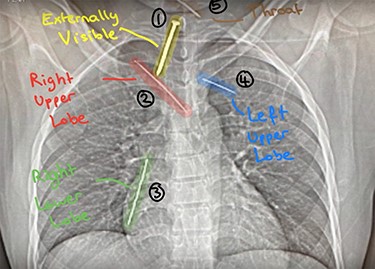

This is a report of a 31-year-old male refugee with a history of psychiatric problems, who was admitted to the Intensive Therapy Unit after being found on a motorway. He was in severe chest pain after escaping extreme torture from his home country. On examination, he found to have a nail (Nail 1) penetrating the anterior chest wall (Fig. 1). On further imaging (Fig. 2), he had three further nails in his thorax (Nail 2: right upper lobe, Nail 3: right lower lobe, Nail 4: left upper lobe).

Image of Nail 1: externally visible penetrating anterior chest wall.

Chest X-ray: detailing the position of four nails within the thorax (Nail 2: right upper lobe; Nail 3: right lower lobe; Nail 4: left upper lobe) and Nail 5 (throat).